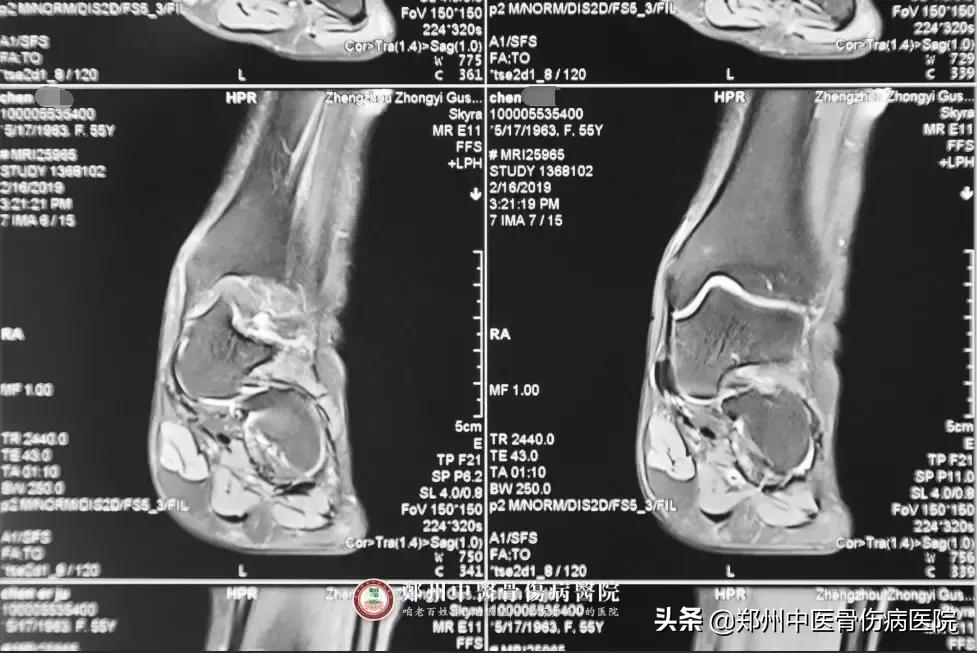

患者片子

陈女士的病情为什么久治不愈?陈志令主任经过影像学资料和体格检查,综合分析后发现症状原因,最终确诊为:1.左踝关节滑膜炎;2.左足骰骨错位症,随即制定了详细的治疗方案。